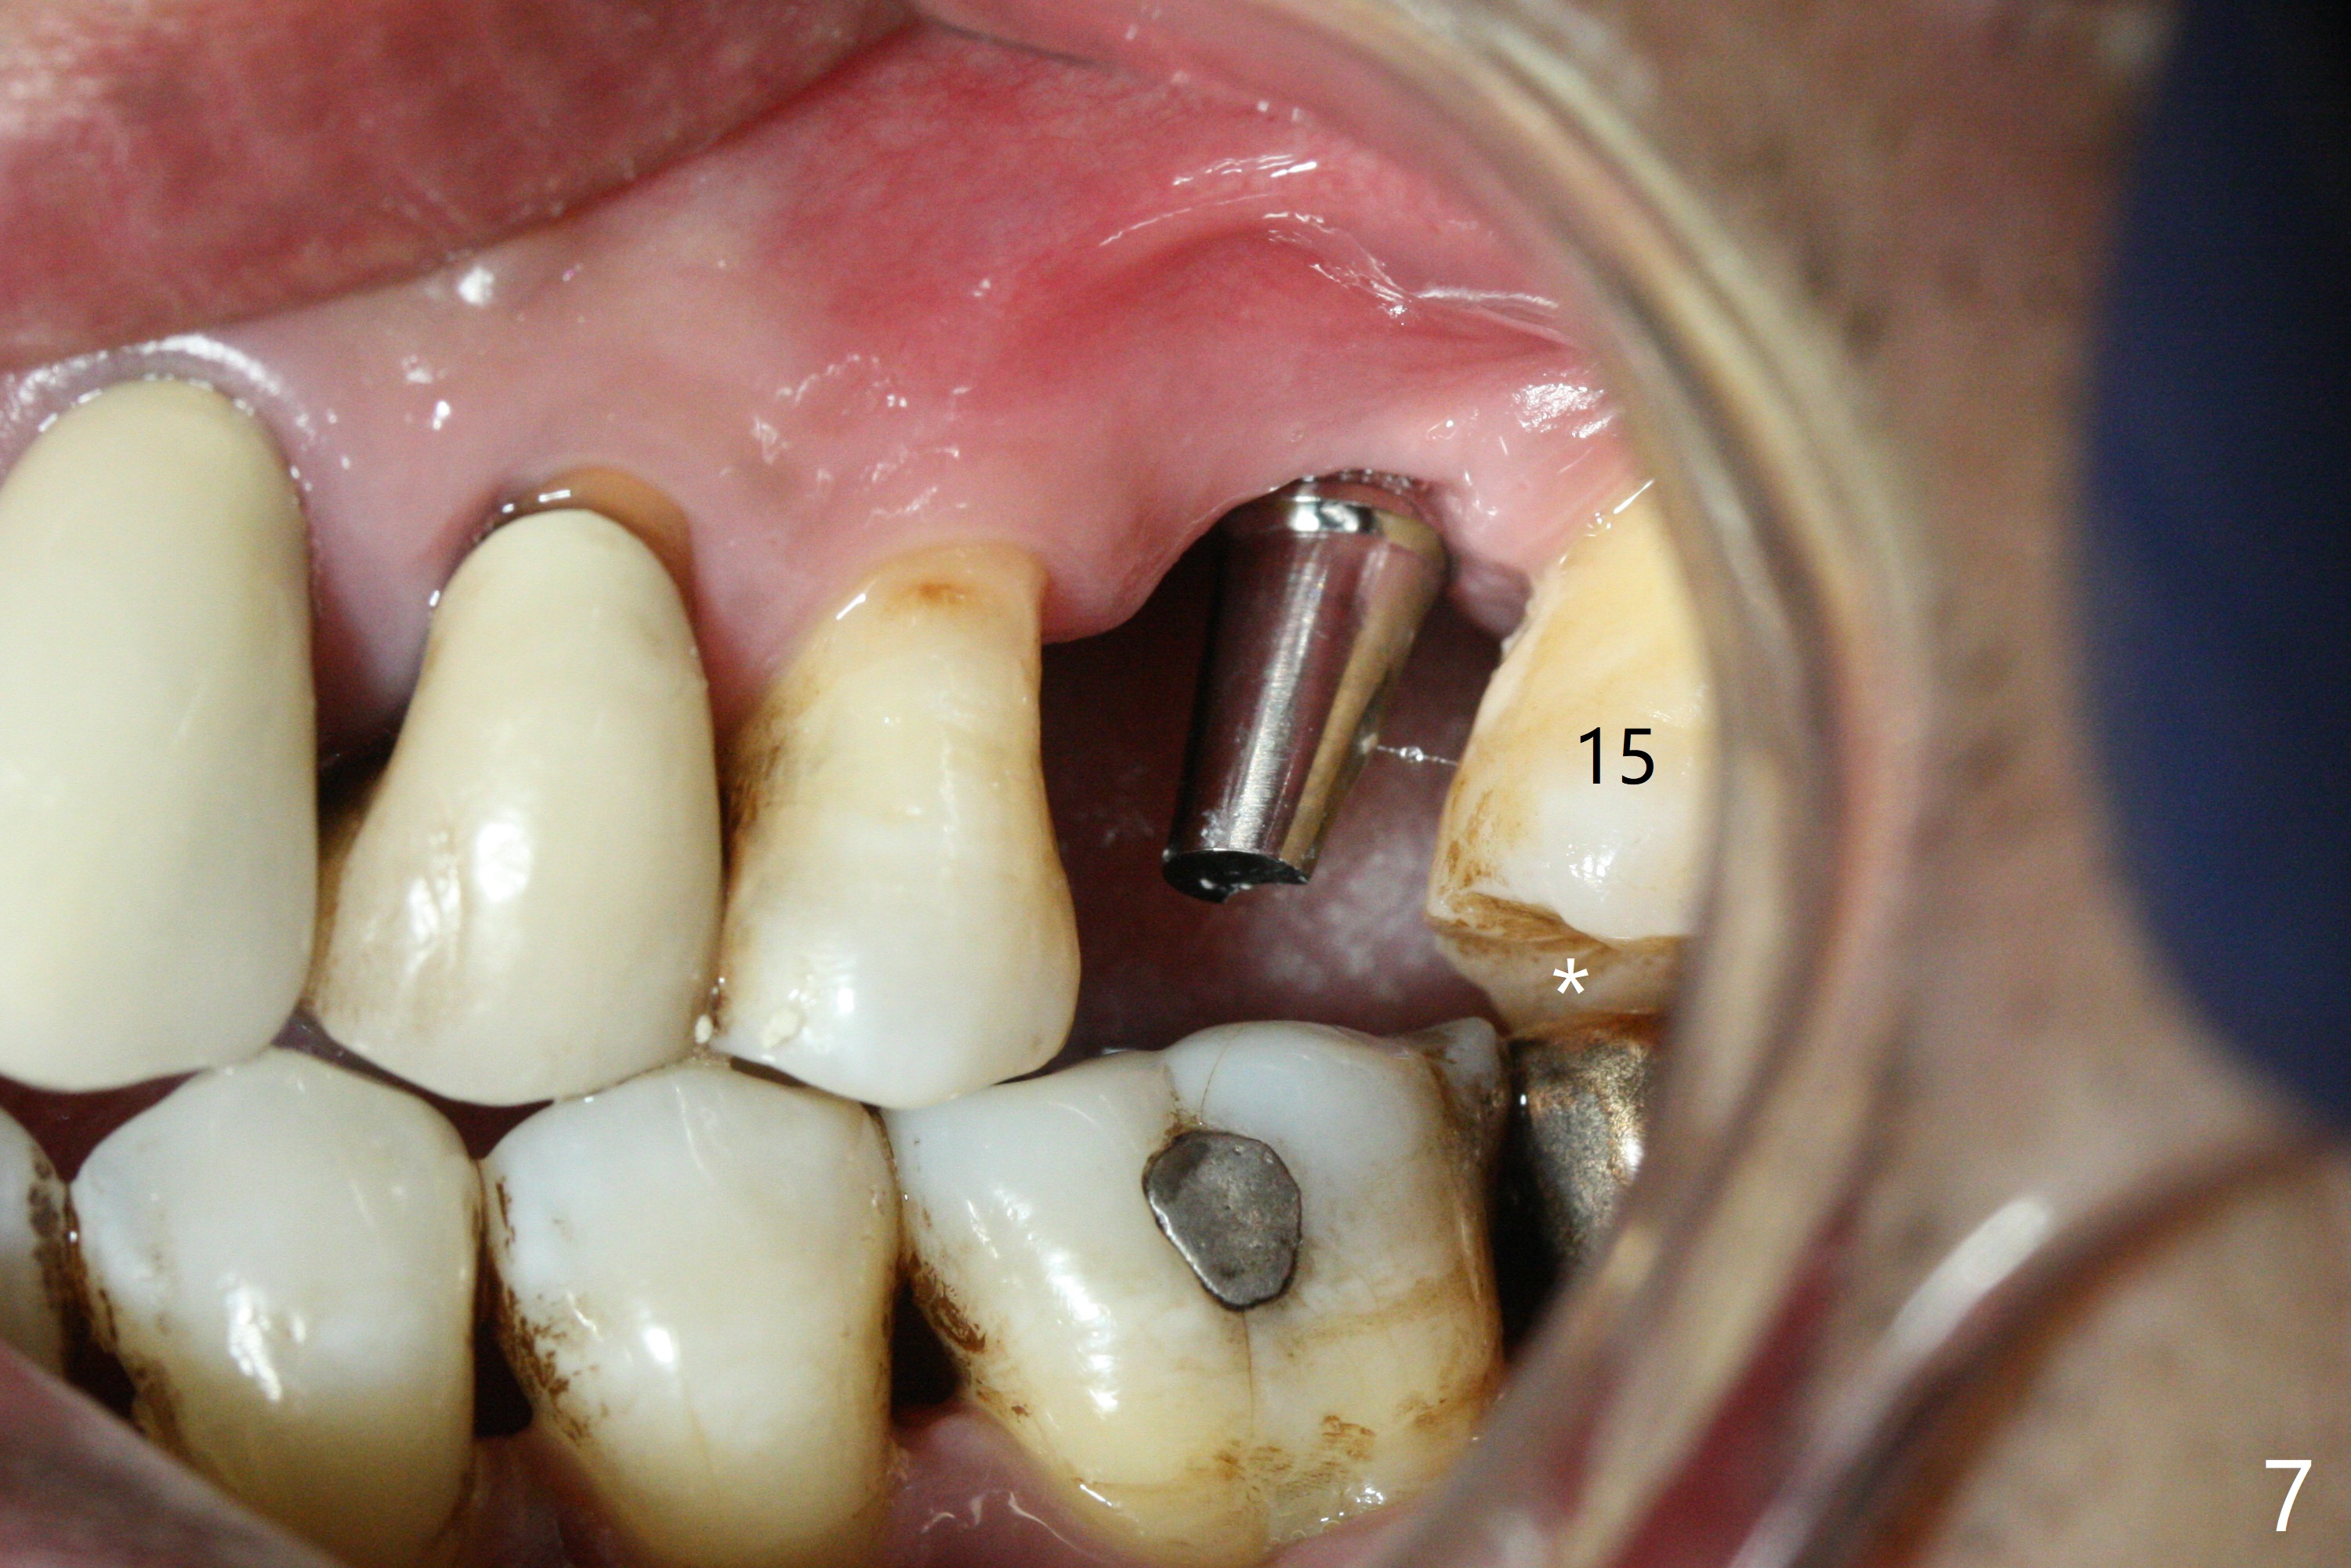

Osteotomy is initiated with Magic Split and 3 mm Magic Expander (ME, flapless) nearly 3 months post socket preservation. To improve the trajectory, the ME is redirected (Fig.1 red line). After use of 3.8 mm ME, Vanilla Graft is placed in the buccal and mesial aspects of the osteotomy. Following reuse of 3 and 3.8 mm MEs, a 4x11 mm dummy implant is inserted with stability (Fig.2 (*: allograft)). More of allograft is placed prior to placement of 5x11 mm IBS implant (Fig.3,4 (~30 Ncm)). The latter is placed palatal. Last the allograft is placed palatal. A 5x4(2) mm abutment is placed to hold periodontal dressing in place. When the ridge is narrow, the implant should be small; 4 mm probably the most appropriate in this case. There is a buccal gap 2 weeks postop (i.e., after dislodgement of periodontal dressing, Fig.5). The implant and abutment appear to be loose ~ 1.5 months postop. The pair abutment is changed to a healing one (5x3mm). The implant seems to be osteotointegrated 3.5 months posotp (Fig.6). Because of the mesial shift of the tooth #15 (Fig.6 arrow (6 months post #14 extraction; anterior open bite)), an angled abutment (5x4mm, 15 degree) is used (Fig.7). Limited orthodontic treatment has to be initiated because the mesially shifted #15 has no occlusal contact mesially (Fig.7 *). A provisional is fabricated with light supra-occlusion. A separator is placed between #14 and 15. Once a space is created in a week, acrylic is added to the distal surface of the provisional and the separator is re-used. In fact the implant is found to be unstable 4.5 months postop (Fig.8,9). The palatal (P) plate is thin and incomplete. The provisional is reduced infraocclusal. Two months the implant remains unstable and is removed.